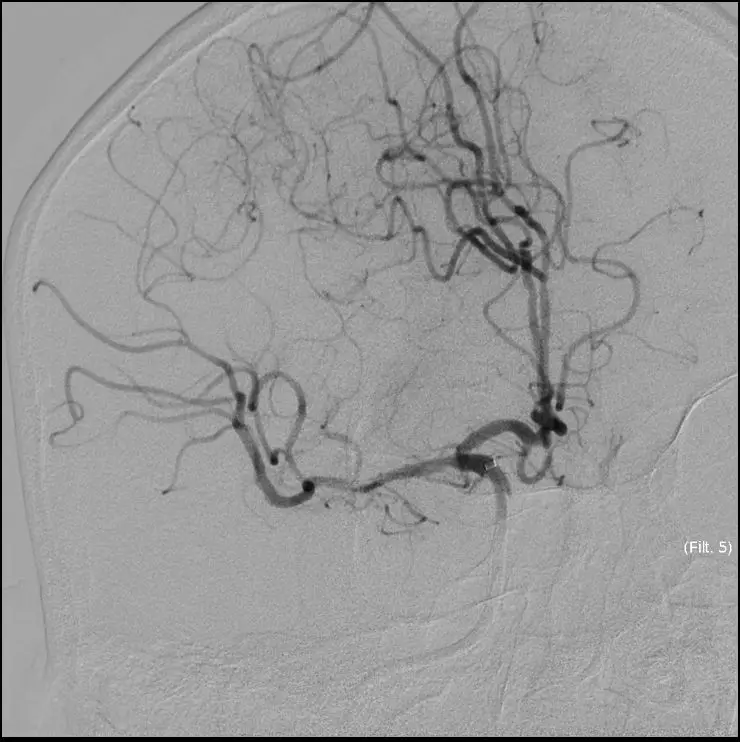

再次与家属沟通病情,交代支架植入风险,家属表示理解,准备支架解脱

5MIN后

再次观察10MIN后

16:30分

手术结束